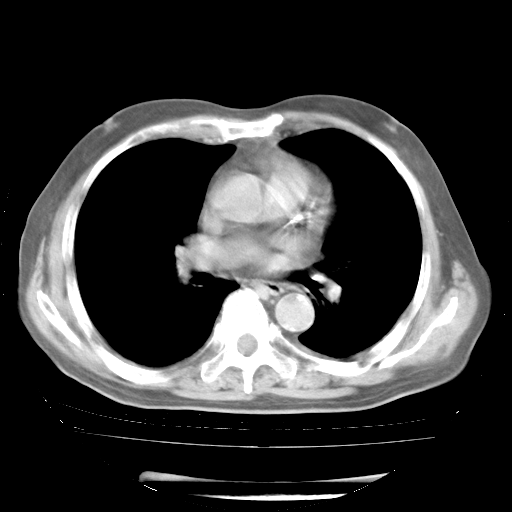

4月28日肺部CT——再次出现类似去年5月9日——透光度降低,“间质性”改变。

4月28日肺部CT——再次出现类似去年5月9日——磨玻璃样、间有“粟粒样”改变。

4月28日肺部CT